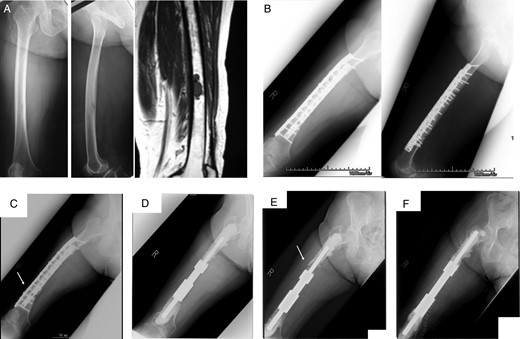

A 54-year-old male with primary soft tissue sarcoma. Plain radiograph (A) and CT (B) showing lytic destructive lesion in left femoral diaphyseal bone. T1- and T2-weighted magnetic resonance imaging (C) showing a soft tissue mass (20 × 20 × 12 cm) around femoral bone. Bone scintigraphy (D) showing increased uptake in femoral diaphyseal bone.

Radiographs showing extracorporeal irradiation after wide resection and stabilization with intramedullary nail (A). At 74 months after operation, radiograph showing fracture of graft bone with broken implant (B and C) and revision with intercalary endoprosthesis (D).